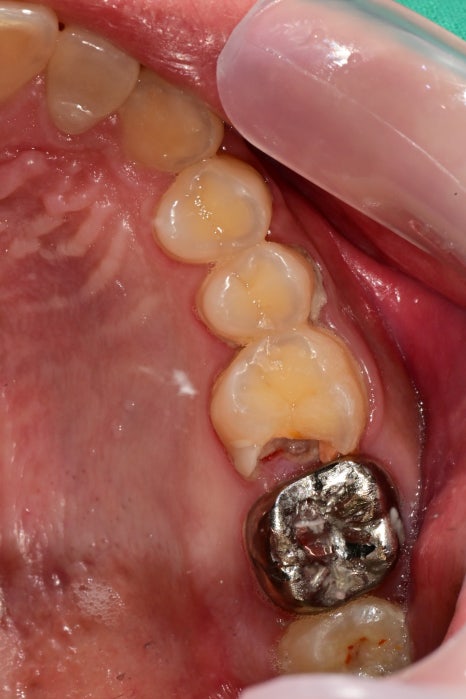

사진과 같이 치석이 많이 쌓여있는 경우

스케일링을 하게 되면

치석이 제거되면서

치석에 의해 눌려있던 잇몸에서 피도 나며

치석이 차지하고 있던 공간이 노출되며

일시적인 시린 증상과 치아 사이가 벌어졌다고 느끼실 수 있지만

치석이 차지하고 있던 부분이기 때문에

필수적으로 제거를 해줘야 합니다!